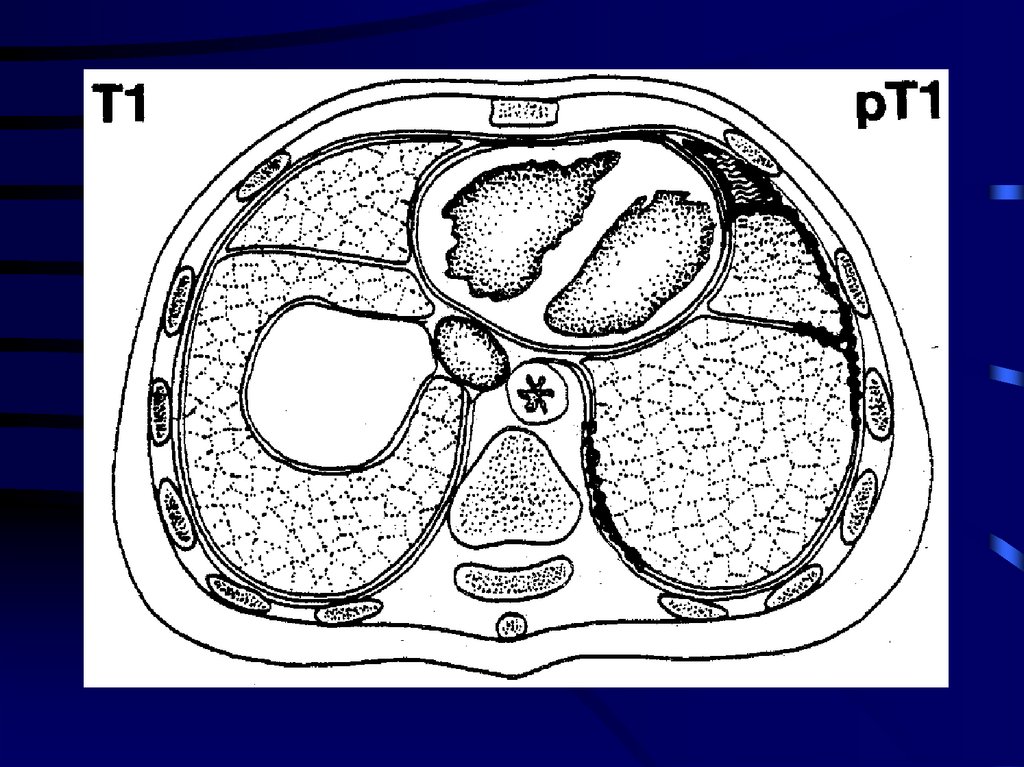

9.

• Опухоль ограничена париетальной и/или

висцеральной плеврой на одной стороне грудной

полости.